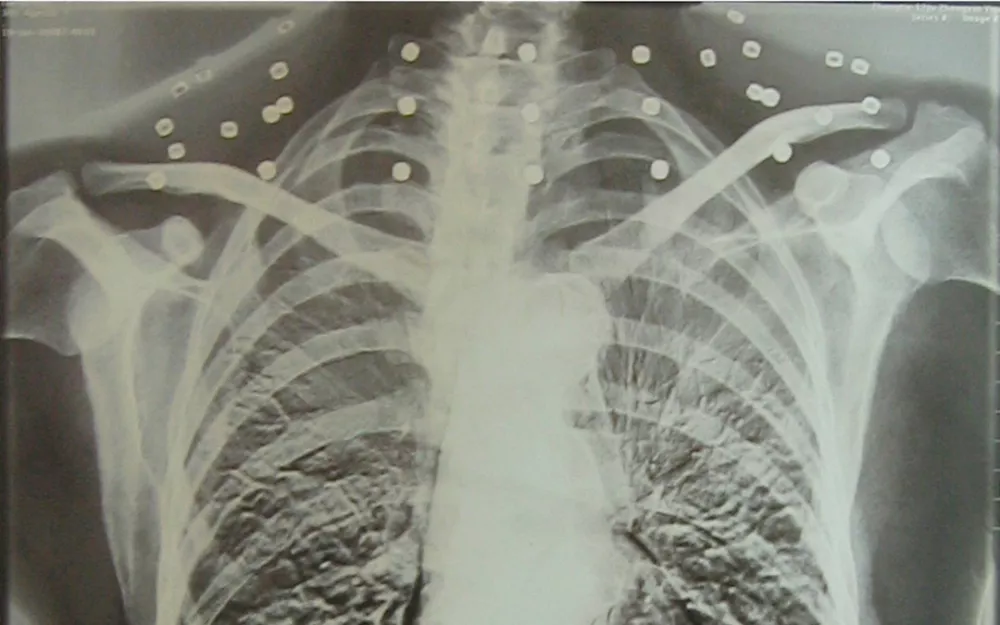

这张照片

是今年82岁的吴以先老人

拍摄的一张CT照

但实际上是

吴以先的颈部和腹部

共分布着33枚弹片

但是打进身体里的弹片

一直留在了体内

他体内的弹片都没有取出

但吴以先不考虑取出弹片

在他看来

这是他与战友并肩作战的见证

是他的勋章

与吴以先身上那33枚弹片